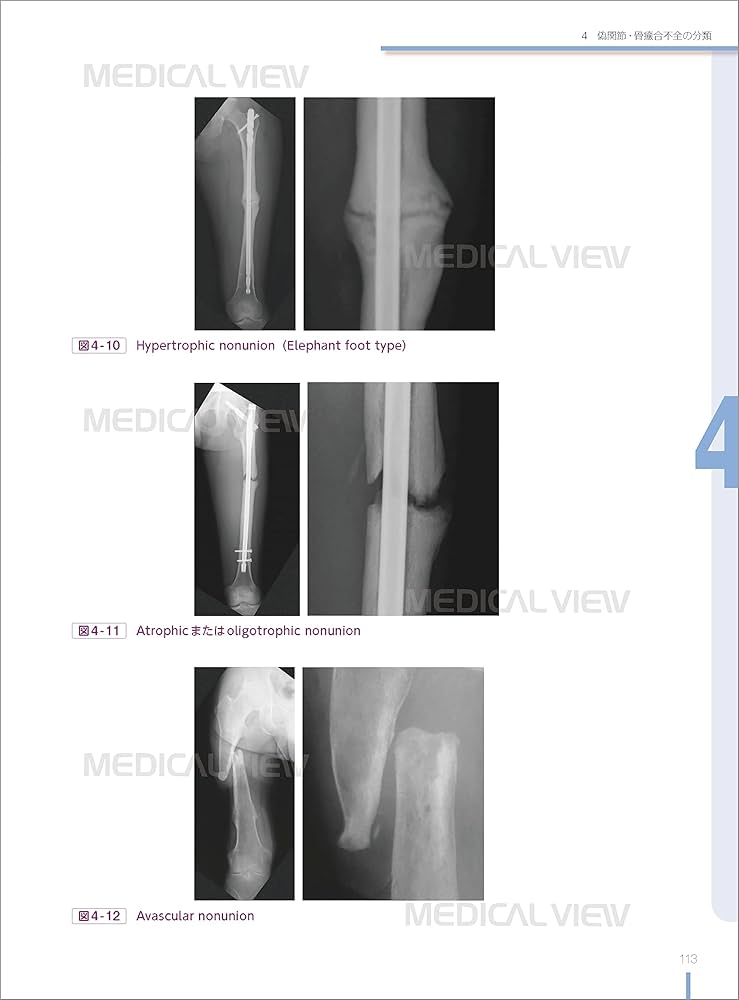

「骨折合併症 : 白熱講義 : 骨折治療の物理学と生物学 : Nonunion,Malunion,FRI,PTOA」渡部 欣忍定価: ¥ 13000裁断済み確認できる範囲で書き込みありません。#渡部欣忍 #渡部_欣忍 #本 #自然/医療・薬学・健康